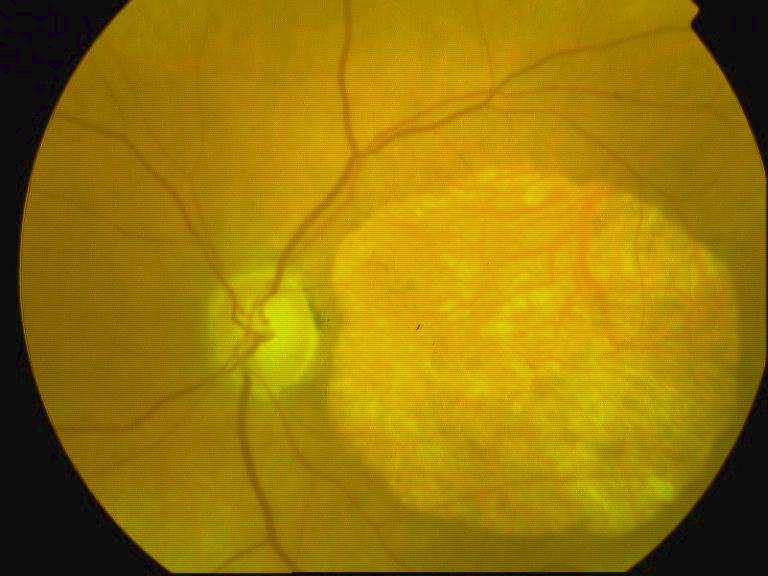

CICATRICE APRES EXERESE CHIRURGICALE DE NEOVAISSEAUX

IM000009.JPG